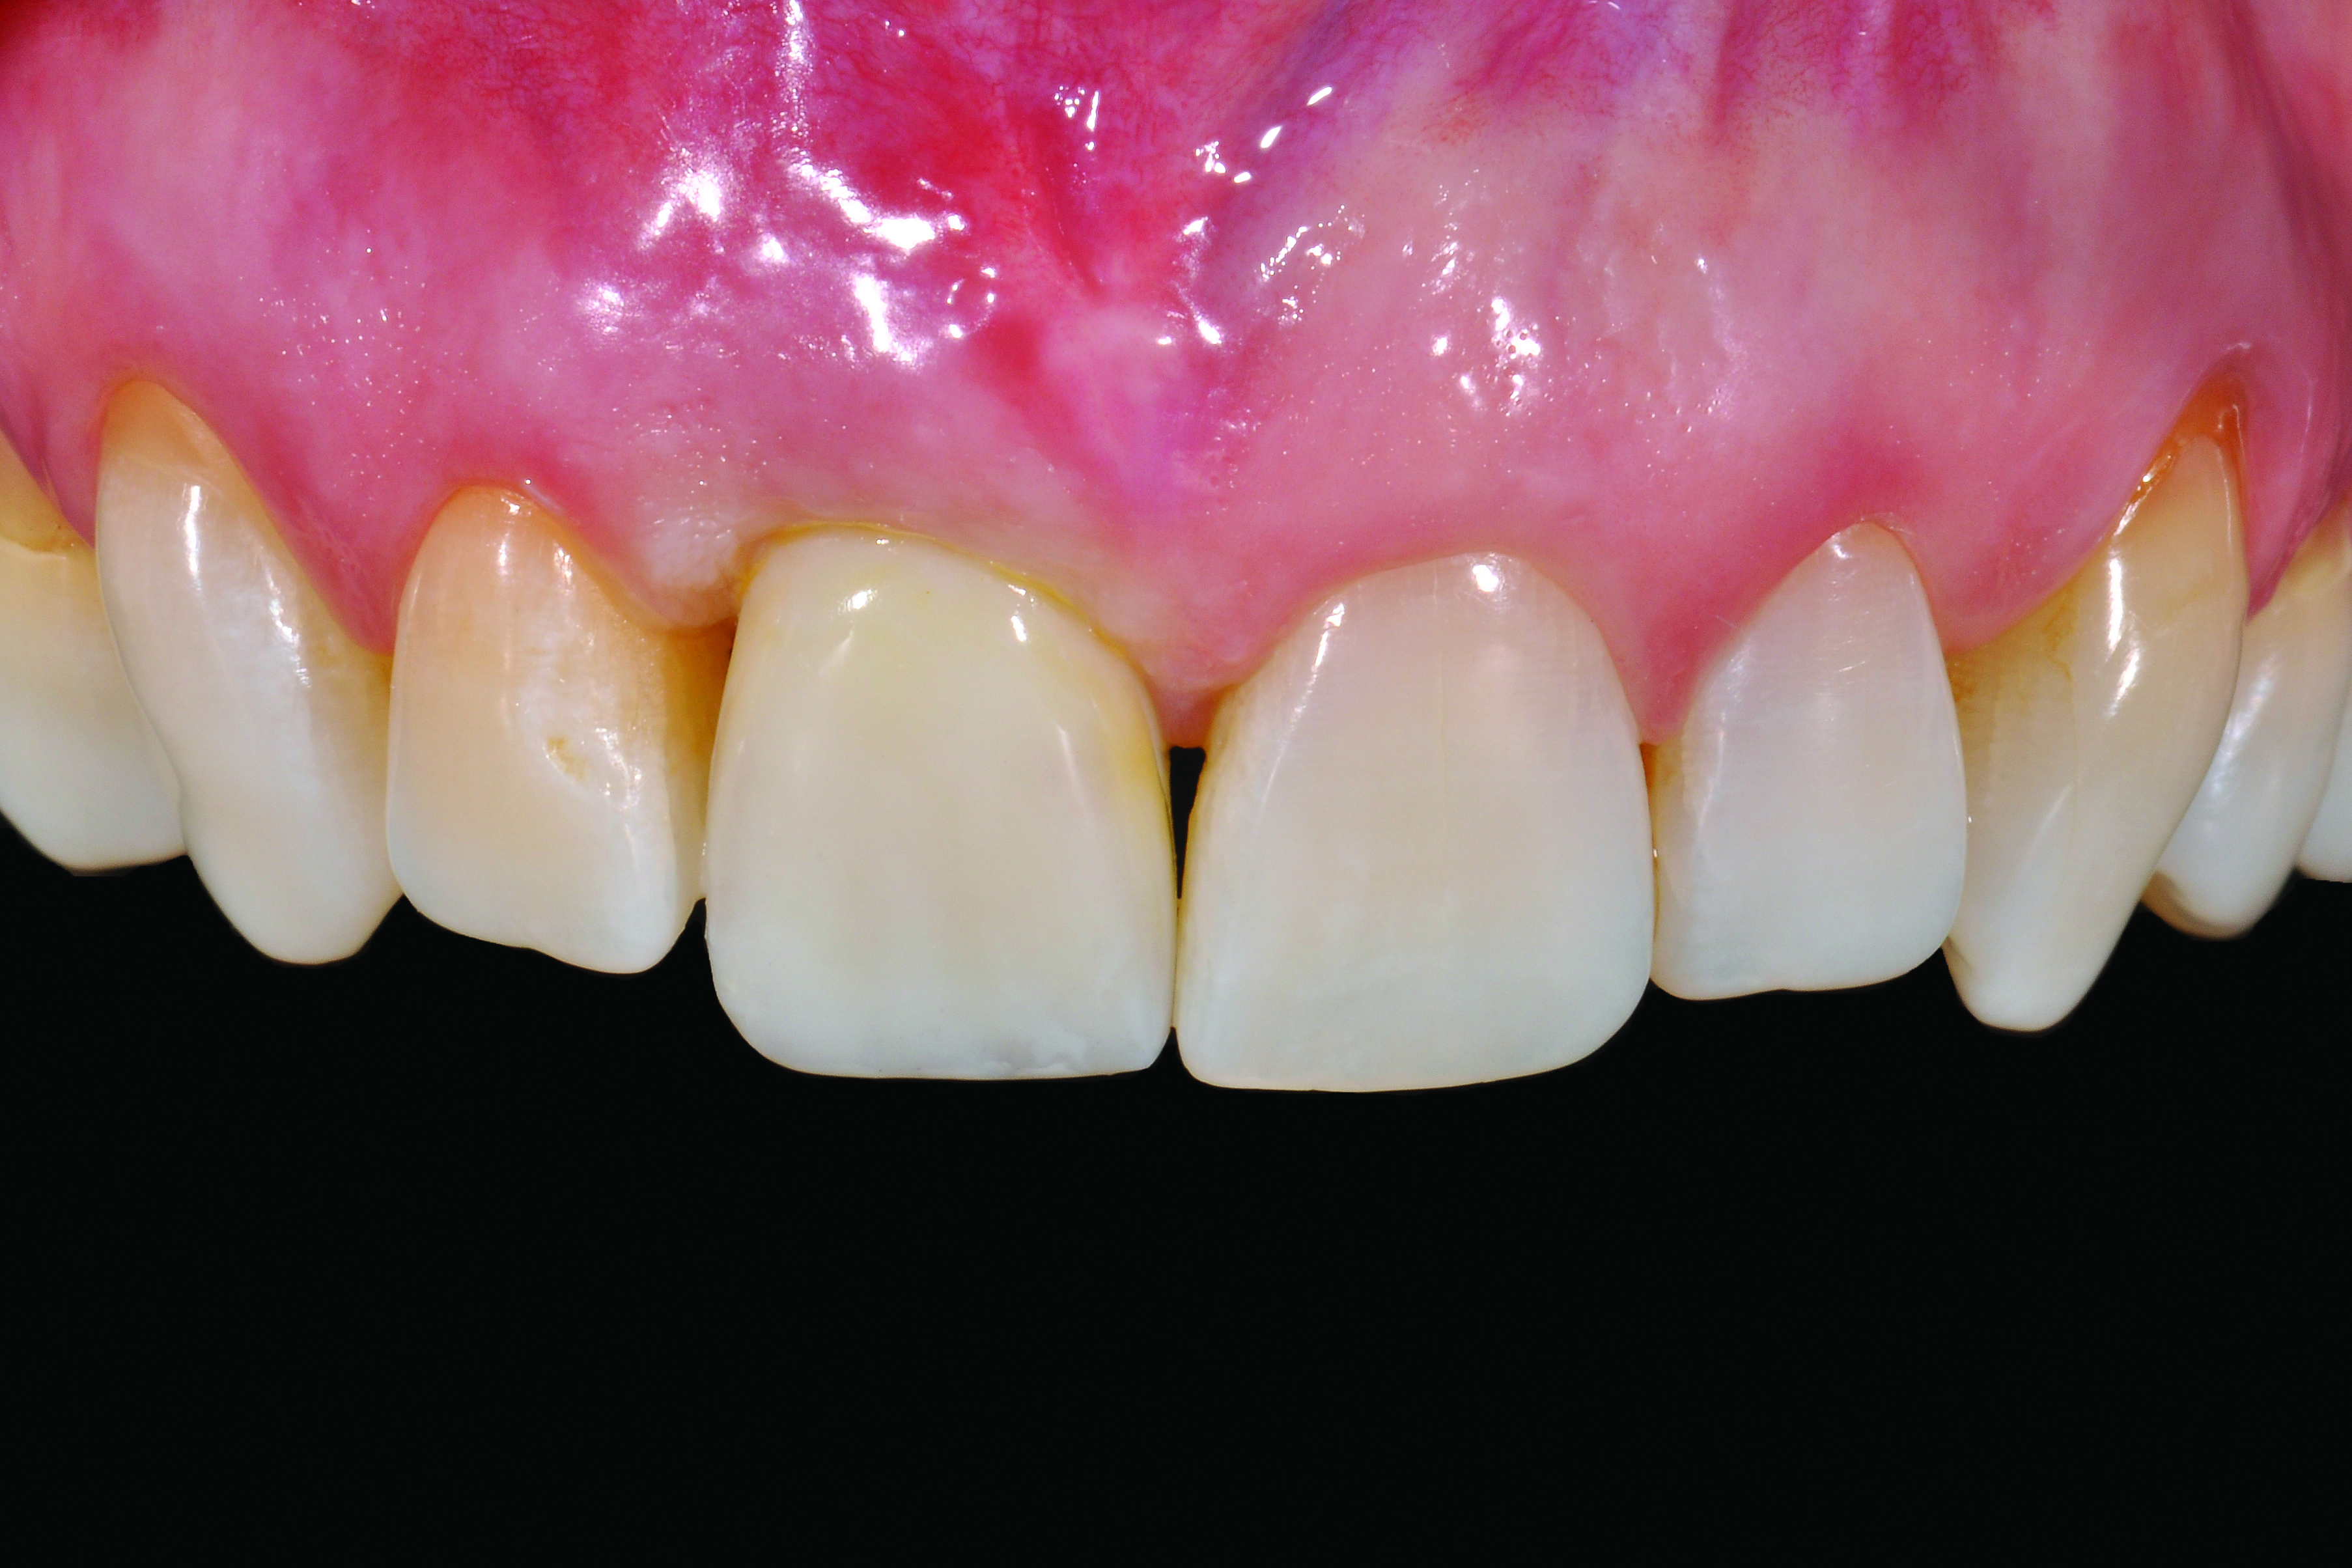

A 57-year-old female was referred to the author’s intramural practice at the University of Iowa College of Dentistry for evaluation of a visually evident, pink lesion associated with the lingual aspect of tooth No. 8 (Figure 1). The patient had no symptoms at the time of the examination. The periodontal status was normal, with isolated areas of facial mucogingival recession (Figure 2). Percussion testing of the maxillary sextant revealed ankylosis of tooth No. 8 based on auditory sounding. A diagnostic cone-beam computed tomography (CBCT) scan was performed. The findings pointed to confirmation of a large external cervical resorption lesion (Heithersay Class IV lesion10) associated with tooth No. 8 (Figure 3), leading to a hopeless long-term prognosis.

Fig 1. Lingual view of maxillary right central incisor with associated pink lesion.

Figure 1